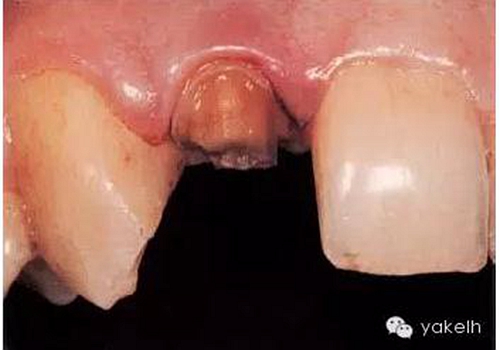

¤¤最終,患者同意12根管再治療后樁核冠修復。臨床上,應在拆除現(xiàn)有修復體、評估冠部剩余牙體量后,方能確定最終治療方案(圖6.3.2)。

圖6.3.2 拆除12現(xiàn)有修復體后剩余的牙體組織。

為什么必須去除現(xiàn)有修復體?

● 評估冠部剩余牙體量,即確定患牙的可修復性。

● 確認牙齒無齲壞,尤其是修復體邊緣有缺損的患牙。

● 髓腔制備時,可最小限度地去除健康牙體組織。原有鑄造冠不能反映牙齒的原始形態(tài)和位置。

● 有助于定位根管口及獲得進入根管的直線通路。

● 根據(jù)剩余牙體量和位置,選擇最合適的方法修復患牙。